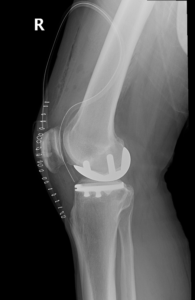

During the surgery, a small incision is made over the knee to expose the knee joint. Your surgeon will remove only the damaged part of the meniscus and place the implant into the bone by slightly shaping the shin bone and the thigh bone. The plastic component is placed into the new prepared area and is secured with bone cement. Now the damaged part of the femur or thigh bone is removed to accommodate the new metal component which is fixed in place using bone cement. Once the femoral and tibial components are fixed in proper place the knee is taken through a range of movements. The muscles and tendons are then repaired and the incision is closed.

Unicompartmental knee replacement, also called a partial knee replacement is surgery to treat arthritis which is limited to one of the knee compartments. During the surgery, only the damaged compartment of the knee is removed and replaced with metal and plastic, leaving the remaining healthy cartilage and bone.